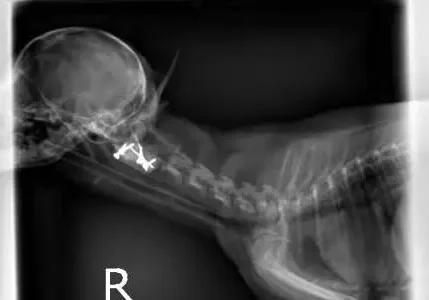

Below are radiographs of Gracie before and after her neck splint was placed. Note the large space between the first two bones in Gracie’s neck prior to reduction.

After Placing the Splint

Gracie after placing a splint. Note that the subluxation is reduced.